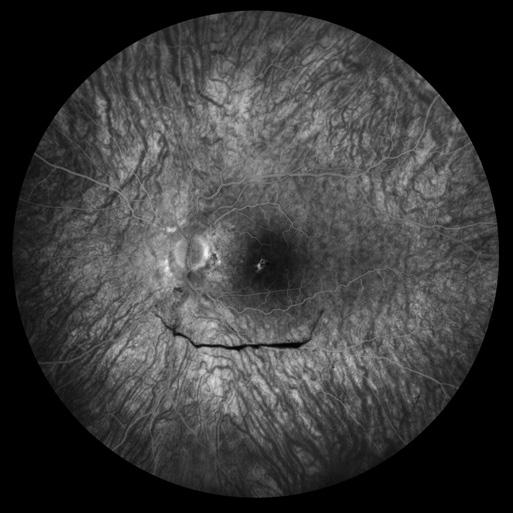

Fundus Autofluorescence

Submacular Hemorrhage

Dena Harris, CRA

University of Michigan Kellogg Eye Center

Ann Arbor, Michigan